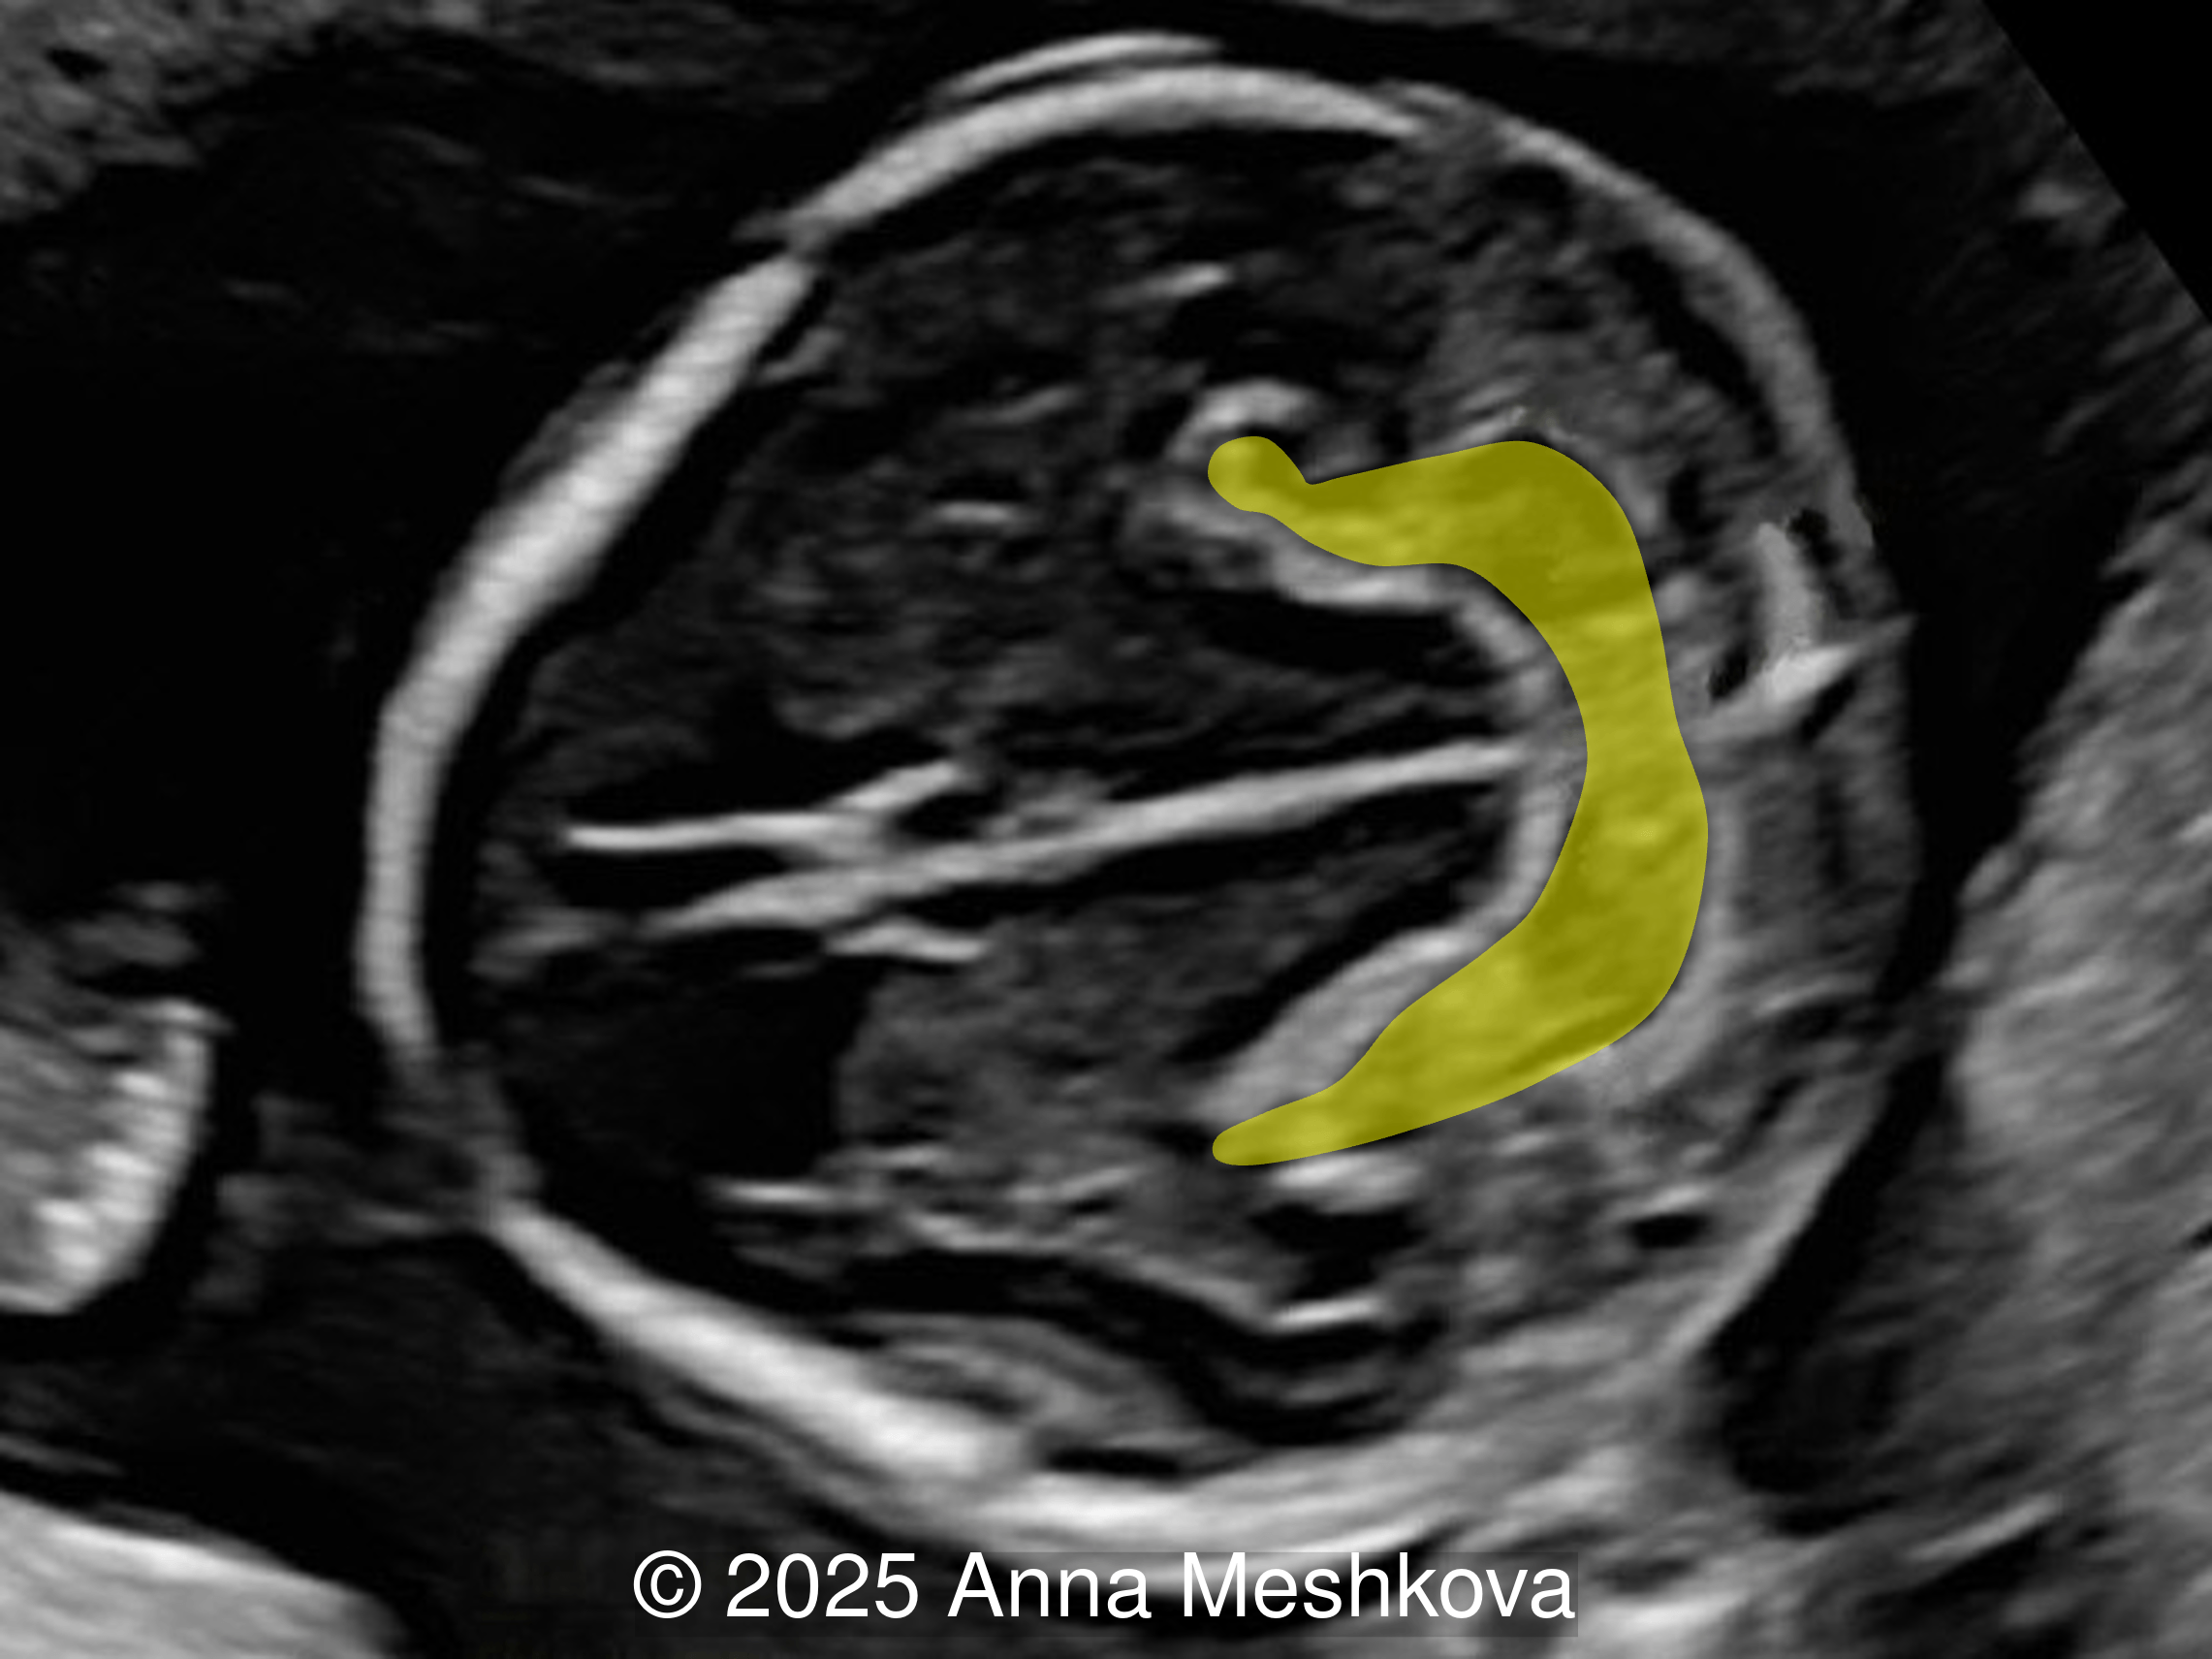

• Image 2:  Transverse section of the brain at the level of the aqueduct of Sylvius. Midbrain is seen juxtaposed to the occiput, known as "crash" sign.

Image demonstrates the Lemon sign with scalloping of the frontal bones and the Banana sign with caudal displacement of the cerebellum (yellow shading).

Image 13 Image demonstrates the Lemon sign with scalloping of the frontal bones and the Banana sign with caudal displacement of the cerebellum (yellow shading).